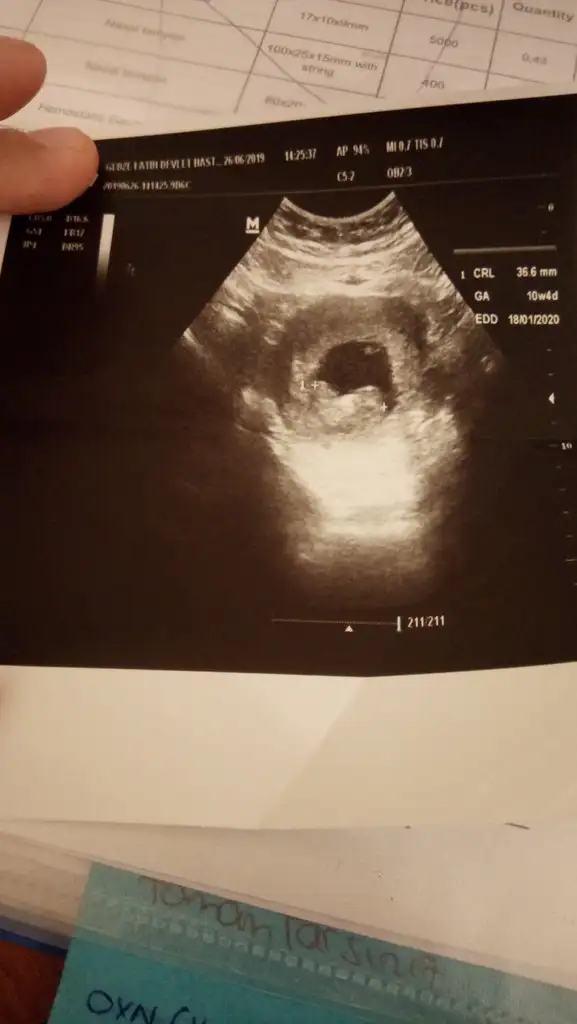

Merhabalar 10+4 de çekilmiş ultrason görüntüsü lütfen tahminlerinizi esirgemeyin

Eklentiler

• IMG-20190627-WA0009.webp

IMG-20190627-WA0009.webp

18,4 KB · Görüntüleme: 69